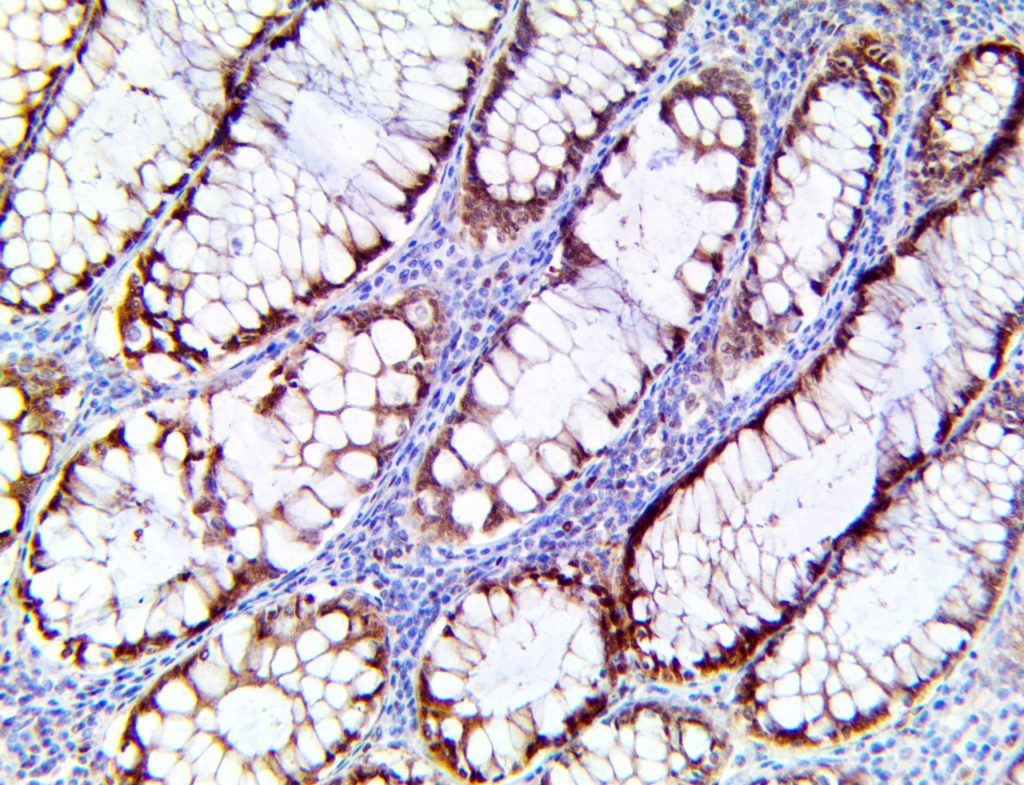

The first cytokines released are interleukin 1β (IL-1β) and tumor necrosis factor-α (TNF-α), which attract a variety of circulating white blood cells (WBCs) to the infection site, including neutrophils, monocytes, macrophages, and natural killer (NK) cells. This response, along with the antipathogenic chemicals released by these cells (i.e., complement), comprise the innate immune response. These cells directly attack the invading pathogen and also release additional cytokines, chief among them interleukin-1 and 6 (IL-6). IL-6 is essential for invoking the adaptive immune response, which calls T-cells, B-cells, and T helper (Th) cells to the infection site. IL-6 also stimulates further recruitment, proliferation and activation of macrophages.

This activation induces inflammatory monocytes to highly express IL-6, starting a localized and then systemic cascade effect that results in hyperproduction of IL-6, which accelerates the inflammatory process. Because IL-6 also increases vascular permeability, excessive levels cause blood vessels to become very leaky. This, along with clotting factors released from vascular endothelial cells, stimulates the coagulation cascade, resulting in microthrombosis (tiny clots), which leads to ischemia and tissue death of the kidney, intestines, heart, liver, brain and extremities.